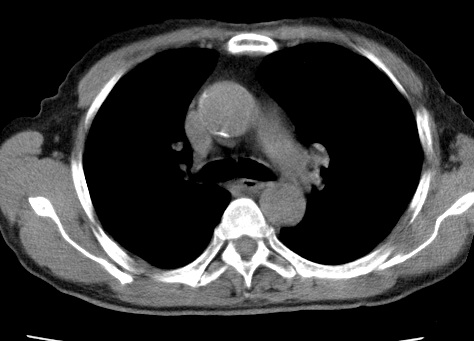

考虑右肺中叶不张,请大家发表意见

右肺中叶不张、肺门轮廓增大,占位不除外;建议增强,必要时支气管镜详查。

右肺中叶支气管闭塞,中叶肺不张,右侧肺门见肿块影。中心型肺癌的可能大。建议支气管镜检查。

右中叶体积明显缩小,且其支气管未显示,先考虑:中心型肺癌班右中叶肺不张。

建议:支气管镜检查。

考虑右肺中叶中央型肺癌并右肺中叶肺不张;建议:行纤支镜检查。

右肺门旁类圆形肿块影,右肺中叶不张,建议纤支镜检查。

1右肺门旁类圆形肿块影,右肺中叶不张,建议纤支镜检查

2右侧胸膜增厚,右侧叶间胸膜区钙化

3右肺下叶小囊状透亮影考虑肺气肿